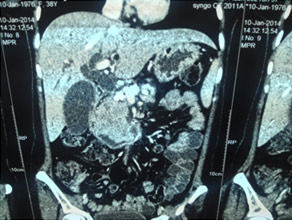

CT scan of pancreatic cancer in the body

Large Neuroendocrine tumour in pancreatic head